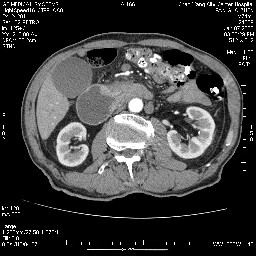

女,74岁,呕吐10余日

十二指肠水平段腔内占位伴梗阻,中等度较为均匀的强化,洗脱慢,区域淋巴结显示增多,符合腺癌表现。下腔静脉变异。

十二指肠降段扩张,水平段狭窄成鼠尾状,肠壁明显增厚,胰腺勾突增大成不均匀强化,其内可见低密度区,胆囊增大,1十二指肠水平段腺癌侵犯胰腺勾突可能大,2胰腺癌侵犯十二指肠(只有胆囊增大没有肝内外胆管扩张不好解释)代除外.

十二指肠降段扩张,水平段狭窄成鼠尾状,肠壁明显增厚,胰腺勾突增大成不均匀强化,其内可见低密度区,胆囊增大,1十二指肠水平段腺癌侵犯胰腺勾突可能大,2胰腺癌侵犯十二指肠 。

今日手术结果:胰腺钩突癌侵犯十二直肠,腹腔淋巴结转移.